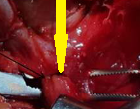

Χειρουργικό παρασκεύασμα οπισθοστερνικής βρογχοκήλης (Ευγενική παραχώρηση Dr. V. Penopoulos)